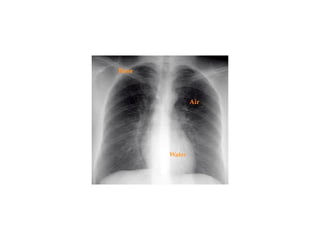

Chest x ray